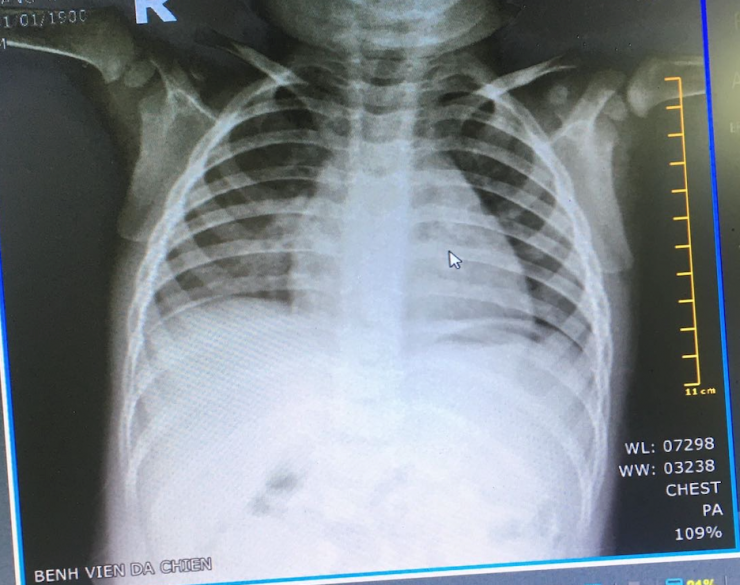

Đặc biệt, hình ảnh X quang phổi sau khi chụp trên xe X quang lưu động của BV dã chiến ngay lập tức được kết nối từ xa về màn hình các bác sĩ chuyên khoa chẩn đoán hình ảnh của các BV Nhi đồng 1 và BV của quận Thủ Đức để đọc kết quả.

Hình ảnh X quang phổi được chụp tại BV dã chiến và được kết nối từ xa với BS chuyên khoa X quang để hội chẩn kết quả